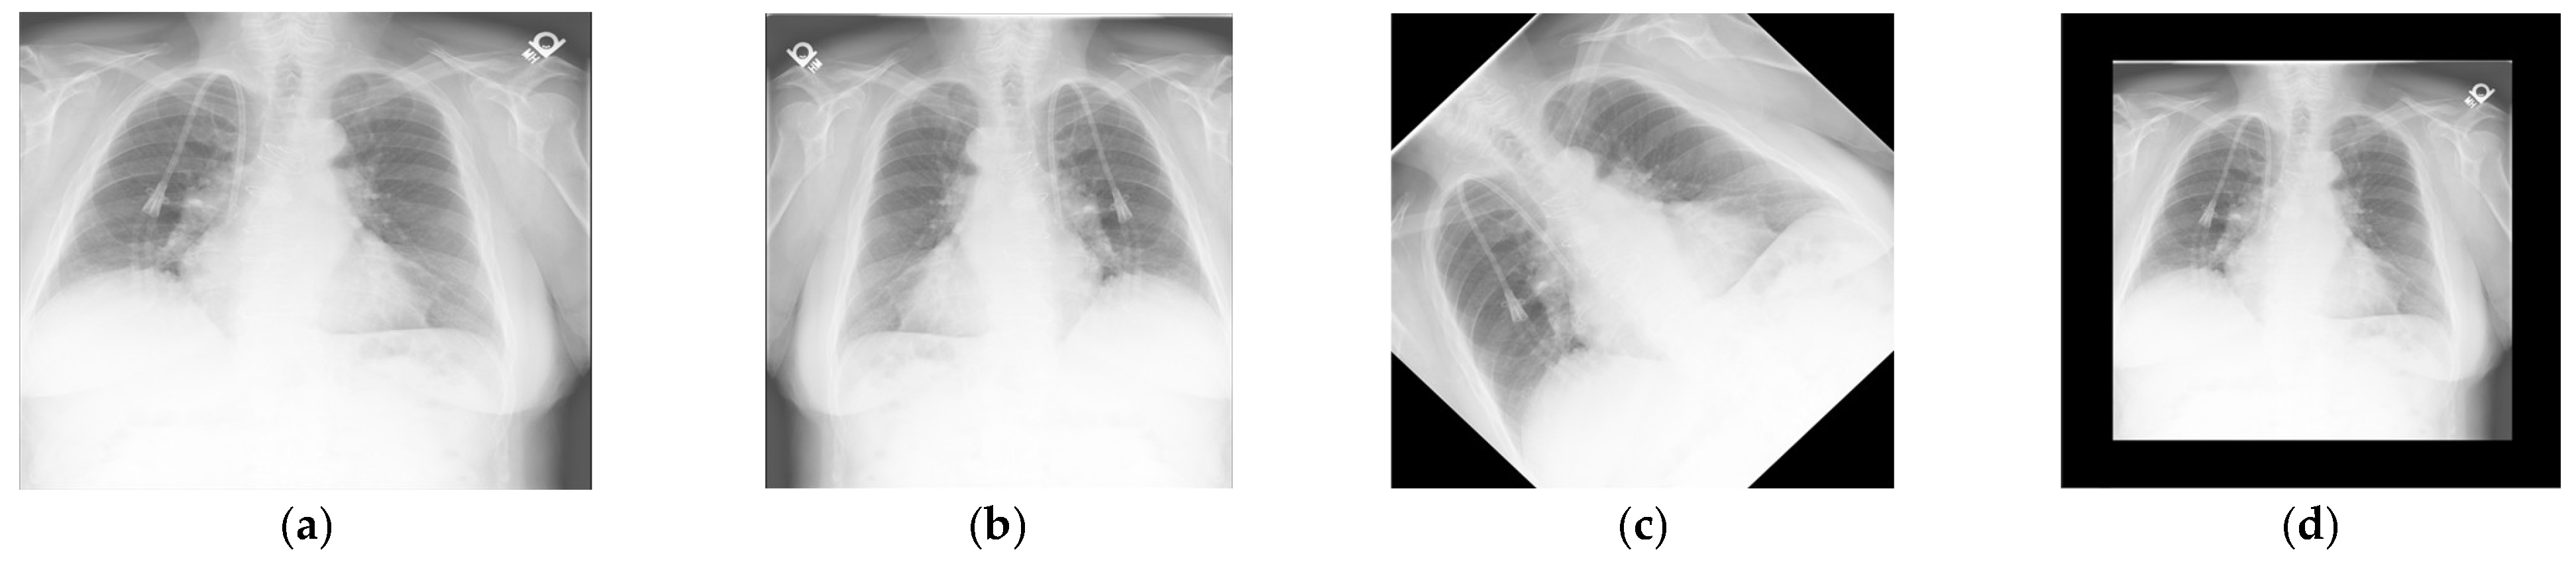

Automating the generation of medical reports from X-ray images offers a promising solution to alleviate this burden. Unlike face-to-face consultations, medical imaging provides a structured foundation for automated interpretation. Chest X-rays are widely used to visualize internal anatomical structures, including the lungs, bronchi, heart, blood vessels, and thoracic cavity. Figure 1 illustrates a typical chest X-ray image used in clinical practice.

Figure 1. Sample chest X-ray images from the open-access Indiana University Chest X-ray Collection. Source: https://openi.nlm.nih.gov/ [1].